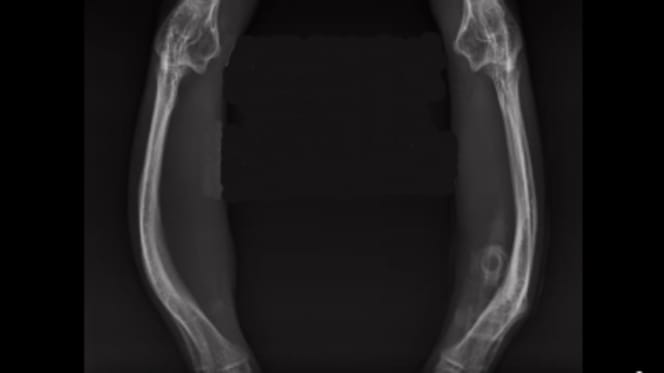

Was auf dem leuchtenden Monitor im Röntgenraum erscheint, gleicht einem unbegreiflichen Puzzle. Eine chaotische Knochen-Anordnung, die so unmöglich scheint. Die Vorderbeine sind drastisch nach außen gebogen, die Hinterbeine extrem nach innen gewinkelt. Das Urteil am Leuchtschirm ist fassungslose Stille.

„Es sieht alles aus“, sagt ein Freiwillige des Tierheims Köln-Dellbrück bei Facebook am 8. April 2026 treffend, „als wäre alles verkehrt herum eingehängt worden.“ Kätzchen Lucy leidet unter einem angeborenen, massiven Defekt, der einem sofort das Herz schwer macht.

Sie bewegt sich nicht wie andere Katzen. Lucy „tippelt“ eher über den Boden. Um das Rätsel ihres mysteriösen Ganges zu lösen, wird sie umgehend geröntgt. Die Bilder am Monitor sind der schockierende Beweis für eine tragische Deformation.